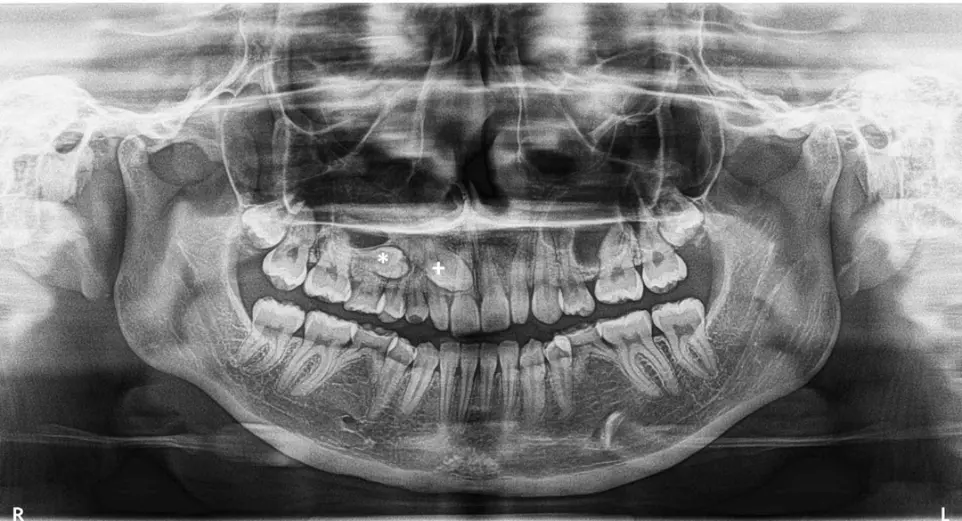

Radiografía Panorámica:

Sabemos que tu tiempo es valioso. Por eso, en nuestro Centro Radiológico eliminamos las esperas. Ofrecemos el servicio de radiografía panorámica (ortopantomografía) con entrega inmediata: llegas, te tomamos la placa y sales con tu estudio impreso o digital en solo 15 minutos. No necesitas agendar cita previa; nuestra tecnología digital está siempre lista para brindarte una visión completa de tus dientes y maxilares al instante.

R: Es el nombre técnico de la radiografía panorámica. Es una sola toma que muestra toda tu boca (dientes, maxilares y articulaciones) en una imagen plana.

Ortopantomografía - Panorámica